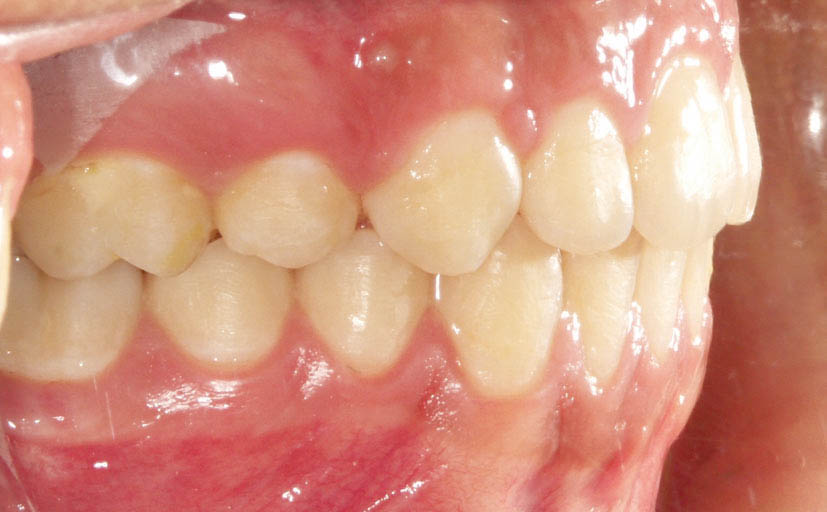

تقریباً بیش از 40درصد افراد جامعه بیماران کلاسII هستند (شکل 21-2 و 22-2).

نبود تورک صحیح، بیشتر در بیماران کلاسII دیده میشود، لذا در ابتدا از این بیماران صحبت میکنیم.

در بیمار کلاسII (جلو بودن ماگزیلا یا عقب بودن مندیبل) جبرانهای دندانی (dental compensation) داریم، یعنی بخاطر اورجت زیاد انسیزورهای بالا رترود و انسیزورهای پایین پروترود میشوند. بدین صورت تا حدی اورجت بیمار کم میشود.

شکل 21-2: رابطه کلاسII مولری

شکل 22-2: رابطه کلاسII مولری